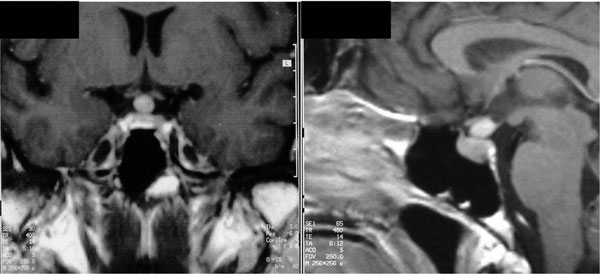

Magnetic resonance imaging (MRI) of the hypothalamic-pituitary region revealed an enlarged pituitary gland with a marked and homogeneous enhancement after gadolinium i.v. Indeed, the infundibulum was enlarged with a maximum diameter of 8 mm and impinged on the optic chiasm (Figure 1). Visual field evaluation revealed a minimal peripheral loss. As MRI did not identify a typical intrapituitary tumor, the patient underwent bilateral inferior petrosal sinus sampling during desmopressin stimulation. The central to peripheral ratio of ACTH was 6.17 on the left side after desmopressin, suggesting a possible corticotropinoma on that side. No pituitary hormones deficiencies were present.

Figure 1. On the left, coronal T1-weighted, contrast-enhanced MR imaging showing a rounded mass located at the level of the pituitary stalk, over the pituitary gland, that appears intact; on the right, sagittal T1-weighted, contrast-enhanced MR imaging confirming the presence of a round mass located at the level of the pituitary stalk, over the pituitary gland, which in this plane seems enlarged in volume.